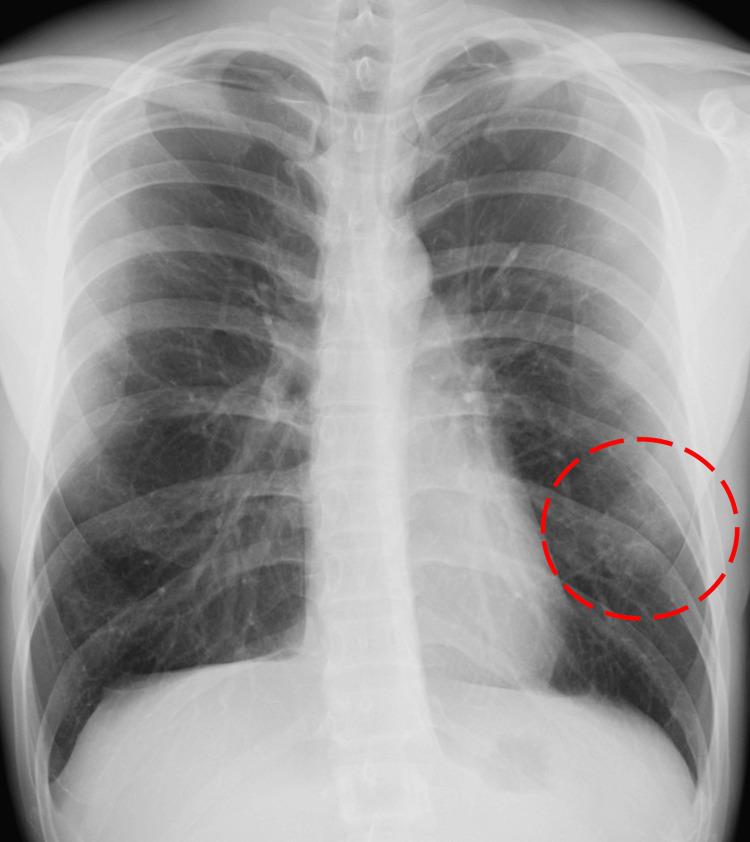

Systemic artery-to-pulmonary vessel fistula (SAPVF) is a rare vascular anomaly, with acquired forms typically arising secondary to intrathoracic inflammation, infection, trauma, or thoracic surgery. We report a case of a 21-year-old man with a history of bilateral video-assisted thoracoscopic surgery (VATS) bullectomy for primary spontaneous pneumothorax who developed bilateral SAPVF. Contrast-enhanced computed tomography revealed abnormally dilated pulmonary vessels with systemic arterial communications in both lungs, corresponding to previous surgical incision sites. On the left side, SAPVF developed despite the surgical wound separated from the lung by oxidized regenerated cellulose sheets. Due to multiple systemic feeding arteries, embolization was considered ineffective, and surgery was avoided owing to the high risk of postoperative reformation. The patient has been managed conservatively, with no progression observed over a two-year follow-up period. This case highlights that SAPVF can occur even after minimally invasive surgery such as VATS, emphasizing the need for careful follow-up and further evaluation of optimal preventive strategies.

体动脉-肺血管瘘(SAPVF)是一种罕见的血管异常,后天性形式通常继发于胸内炎症、感染、创伤或胸外科手术。我们报告一例21岁男性,有原发性自发性气胸双侧电视辅助胸腔镜手术(VATS)肺大疱切除术病史,发生了双侧SAPVF。对比增强计算机断层扫描显示双侧肺内肺血管异常扩张并与体动脉相通,对应于先前的手术切口部位。在左侧,尽管手术伤口被氧化再生纤维素片与肺隔开,但仍发生了SAPVF。由于存在多条体循环供血动脉,栓塞被认为无效,且由于术后复发风险高而避免了手术。该患者一直采取保守治疗,在两年的随访期内未观察到病情进展。该病例突出表明,即使在VATS等微创手术后也可能发生SAPVF,强调了仔细随访以及进一步评估最佳预防策略的必要性。